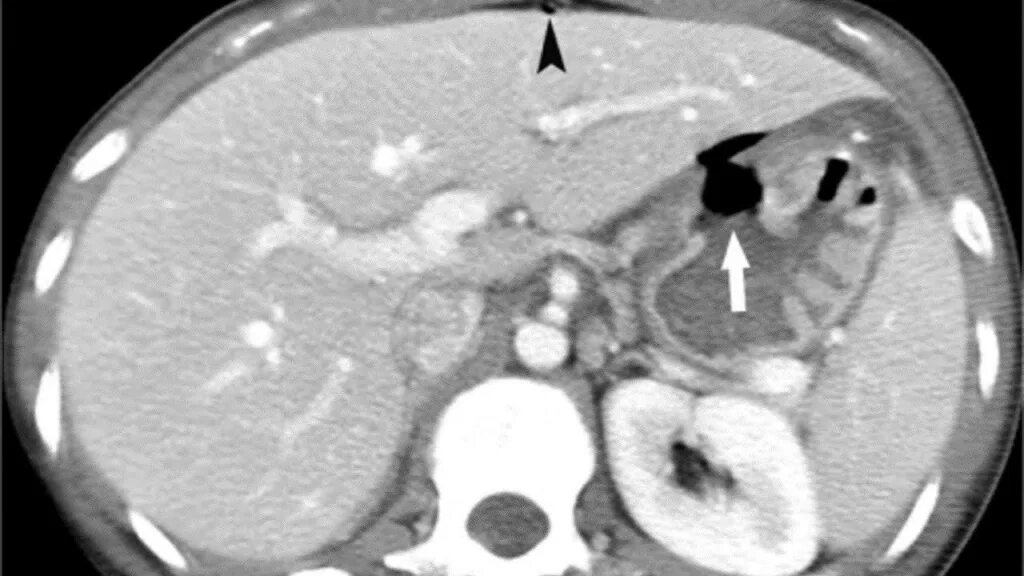

Язва желудка кт